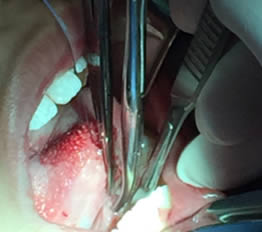

• Se colocó anestesia tópica y se infiltró localmente (lidocaína con epinefrina de 1: 100 000 al 2 %) a cada lado del frenillo lingual bloqueando nervio lingual bilateralmente. (Figuras 1 y 2).

Figura 1. Anestesia Local a cada lado del frenillo.

Figura 2. Anestesia Local del nervio lingual bilateralmente